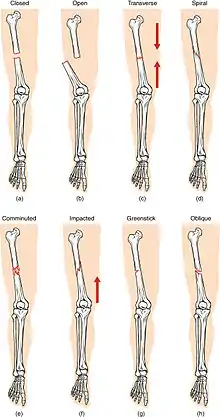

(a) closed fracture

(b) open fracture

(c) transverse fracture

(d) spiral fracture

(e) comminuted fracture

(f) impacted fracture

(g) greenstick fracture

(h) oblique fracture

In orthopedic medicine, fractures are classified in various ways. Historically they are named after the physician who first described the fracture conditions, however, there are more systematic classifications as well.